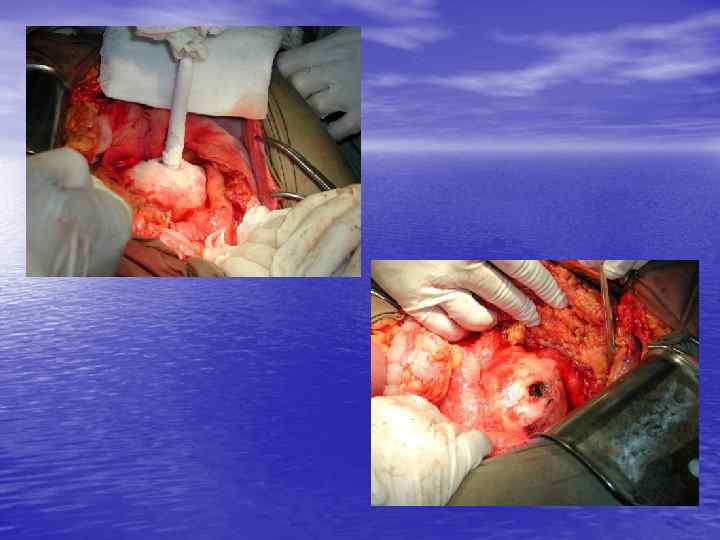

Инвазия чревного ствола и общей печеночной артерии

Резекция чревного ствола и общей печёночной артерии при выполнении ДСРПЖ Вид резекции Циркулярная резекция чревного ствола Всего Число больных с пластикой 4 без пластики 11 15

Верхняя мезентерикография после резекции чревного ствола с ушиванием обоих концов сосуда наглухо. Кровоснабжение печени осуществляется через гастродуоденальную артерию